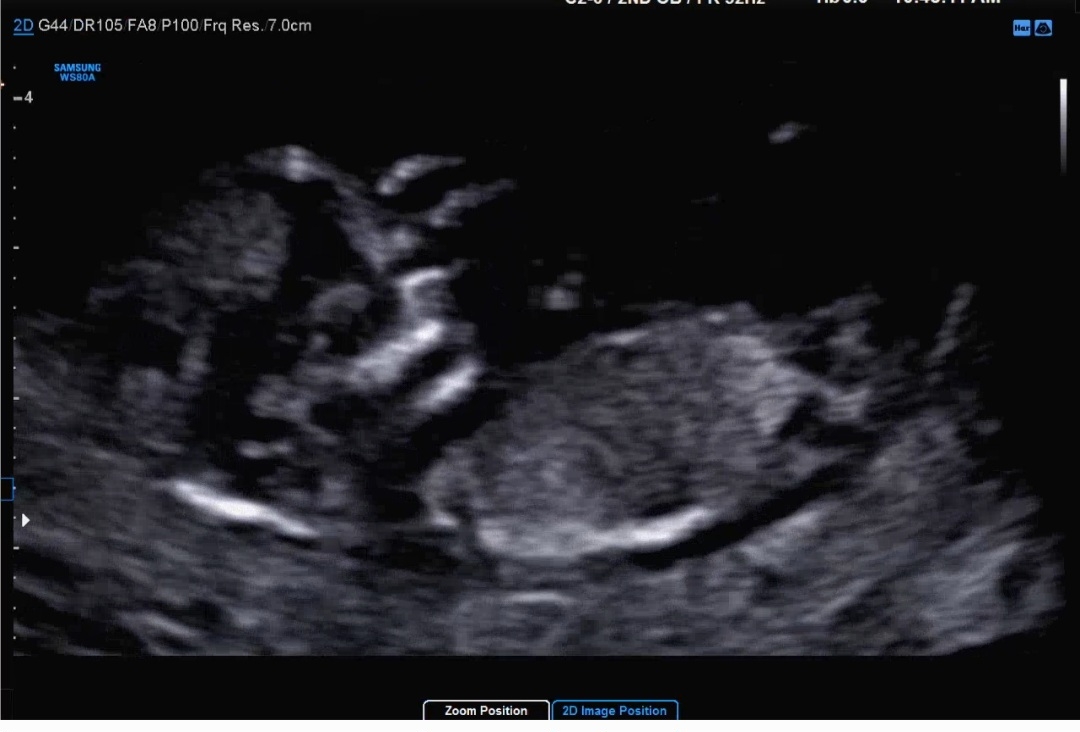

12주차때인데 함 어떻게 보이시나용??

성별 추측부탁드려용 담당 원장님은 딸가능성이 높아보이신다는데ㅋㅋ다른분들이 보기엔 어떤가오??